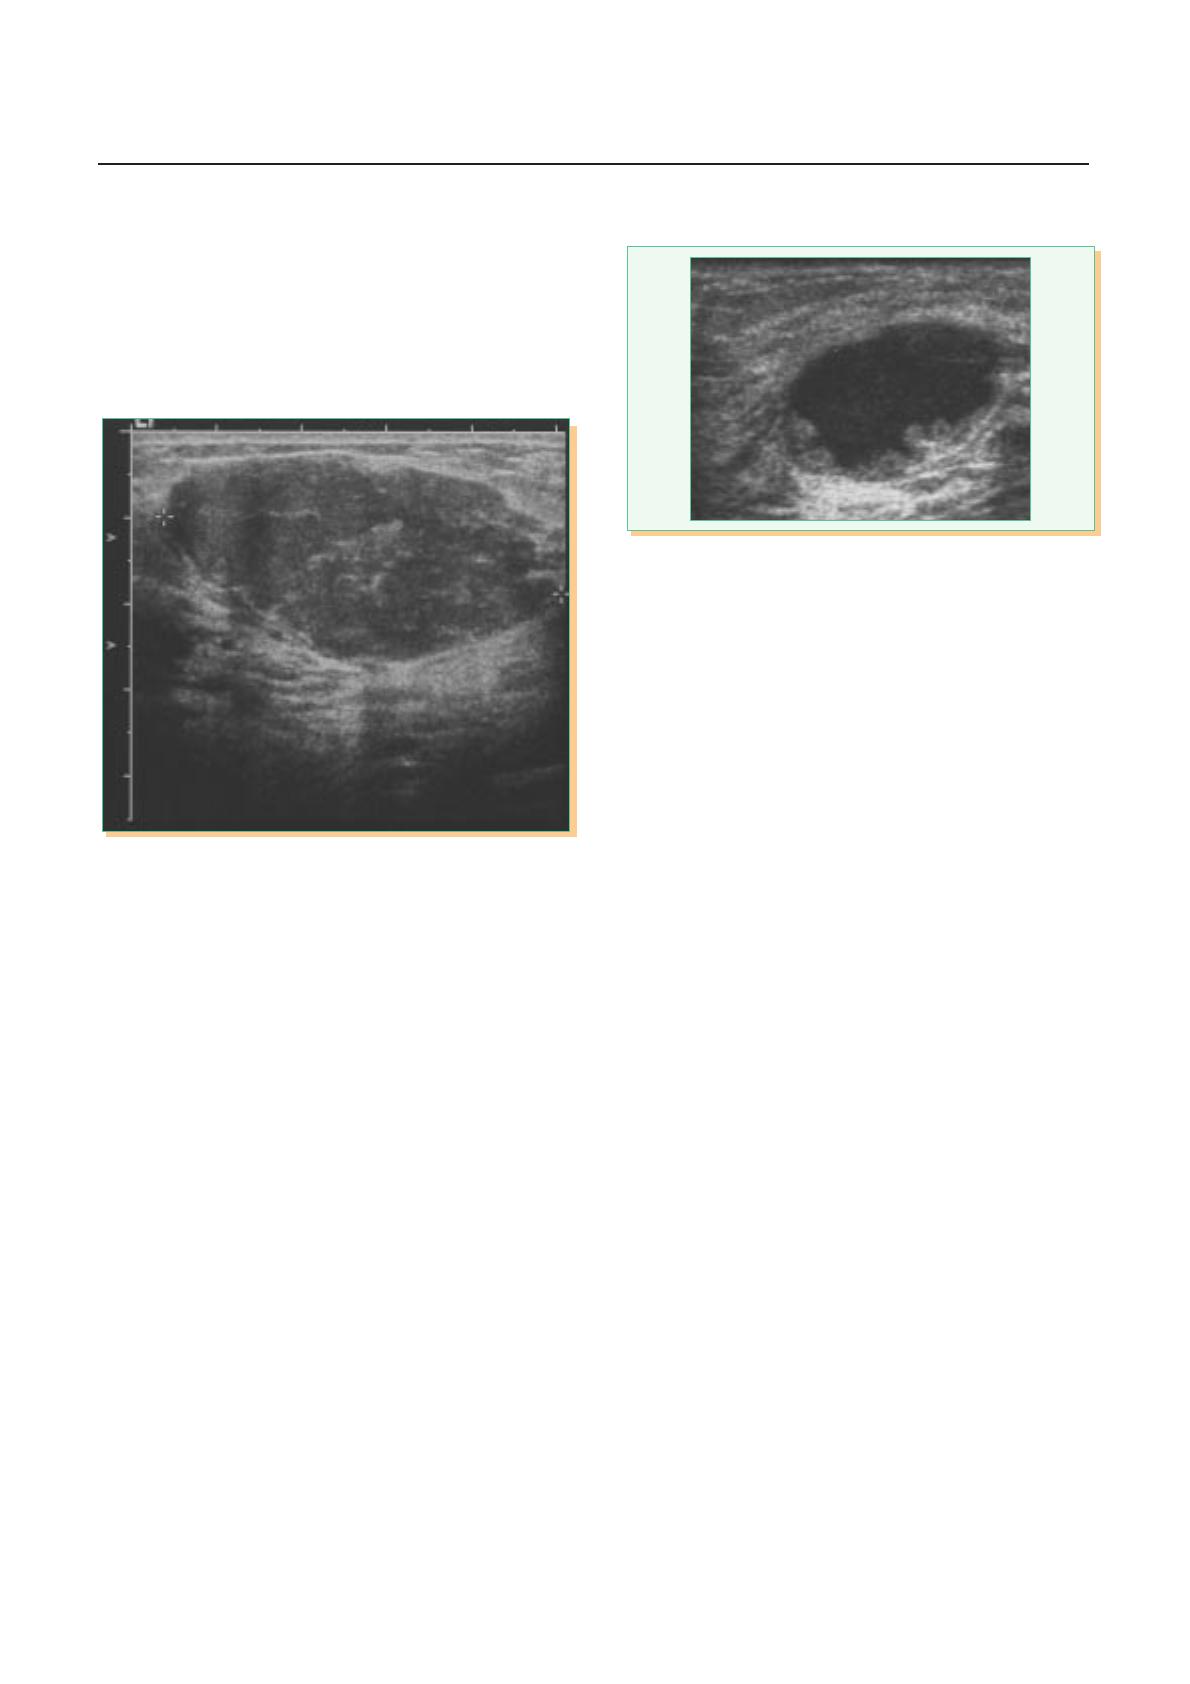

Devant un nodule palpable rétroaréolaire

L’échographie va permettre de trancher sur son caractère solide

ou liquidien. S’il apparaît transsonique pur ou avec un niveau

correspondant à des liquides de phases différentes, on évoquera

un kyste rétroaréolaire (figure 2). On examinera systématique-

ment le côté controlatéral à la recherche d’un kyste asympto-

matique. La ponction à titre diagnostique est inutile.

Figure 2. 15 ans. Nodule rétroaréolaire droit sensible. Échographie :

kyste présentant une image de niveau.